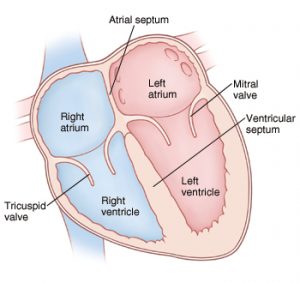

Chambers of Heart

The heart has 4 chambers-2atria[the receiving area]and 2 ventricles, the discharging chambers.

Right atrium

It is the right upper chamber of the heart.Right atrium forms the right border, part of the upper border, the sternocostal surface, and part of the base of the heart . It receives blood from the entire body and pumps it to the right ventricle through the right atrioventricular or tricuspid orifice[opening].

Right Ventricle

The right ventricle forms the inferior border and a large part of the sternocostal surface of the heart. It is a triangular chamber. The pulmonary trunk and pulmonary arteries take deoxygenated blood from the right atrium and pump it to the lungs.

Left Atrium

It represents the left two-thirds of the base of the heart, the greater part of the upper border, parts of the sternocostal and left surfaces, and part of the left border of the heart.

It is a quadrangular chamber receiving oxygenated blood from the lungs through four pulmonary veins and pumps to the left ventricle through the left atrioventricular or bicuspid or mitral orifice, which is guarded by the mitral valve[bicuspid valve].

Left Ventricle

The left ventricle gathers and pumps oxygenated blood from the left atrial into the aorta.

The interior of the ventricle shows two openings:

1. The left atrioventricular or bicuspid, or mitral orifice is guarded by the mitral valve.

2. The aortic orifice, guarded by the aortic valve.